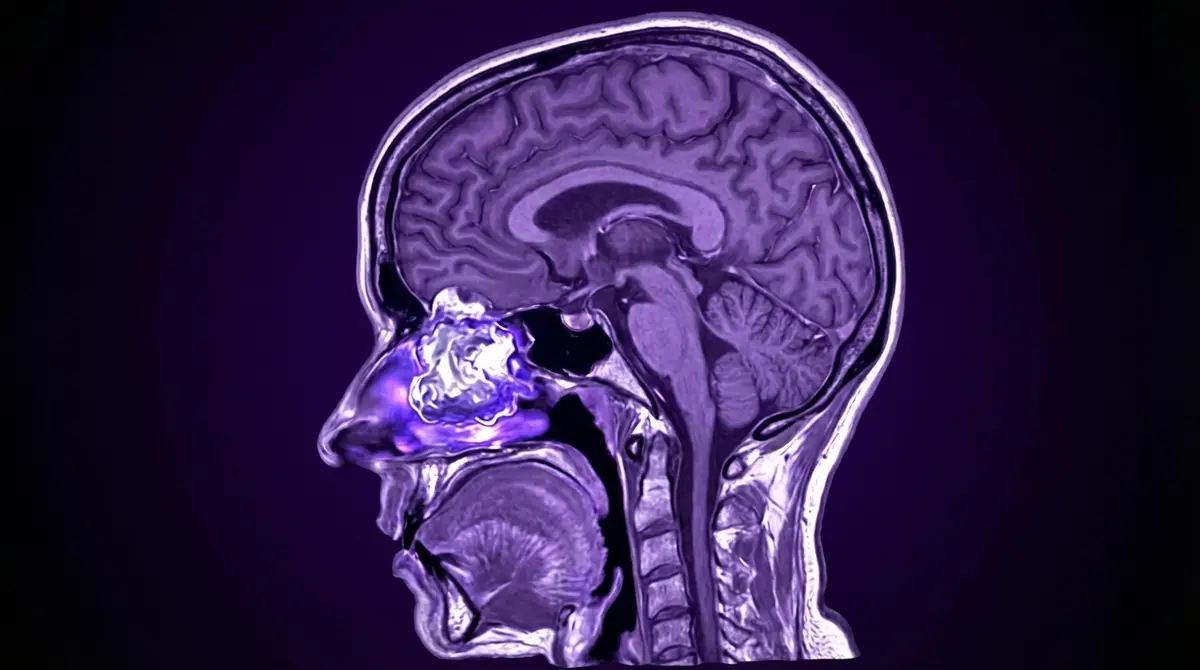

👃 Estesioneuroblastoma

Tumor raro que nasce da mucosa olfativa (tecido de cheiro no topo da cavidade nasal). Apesar de "neuroblastoma" no nome, é diferente do tumor infantil comum. Afeta adultos. Cresce para cima, entrando na fossa craniana anterior, comprimindo o cérebro frontal.

- 🧠 RM da base do crânio (ver extensão intracraniana)